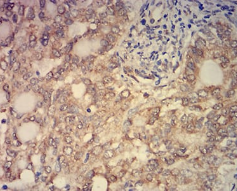

IHC    1/200 - 1/1000